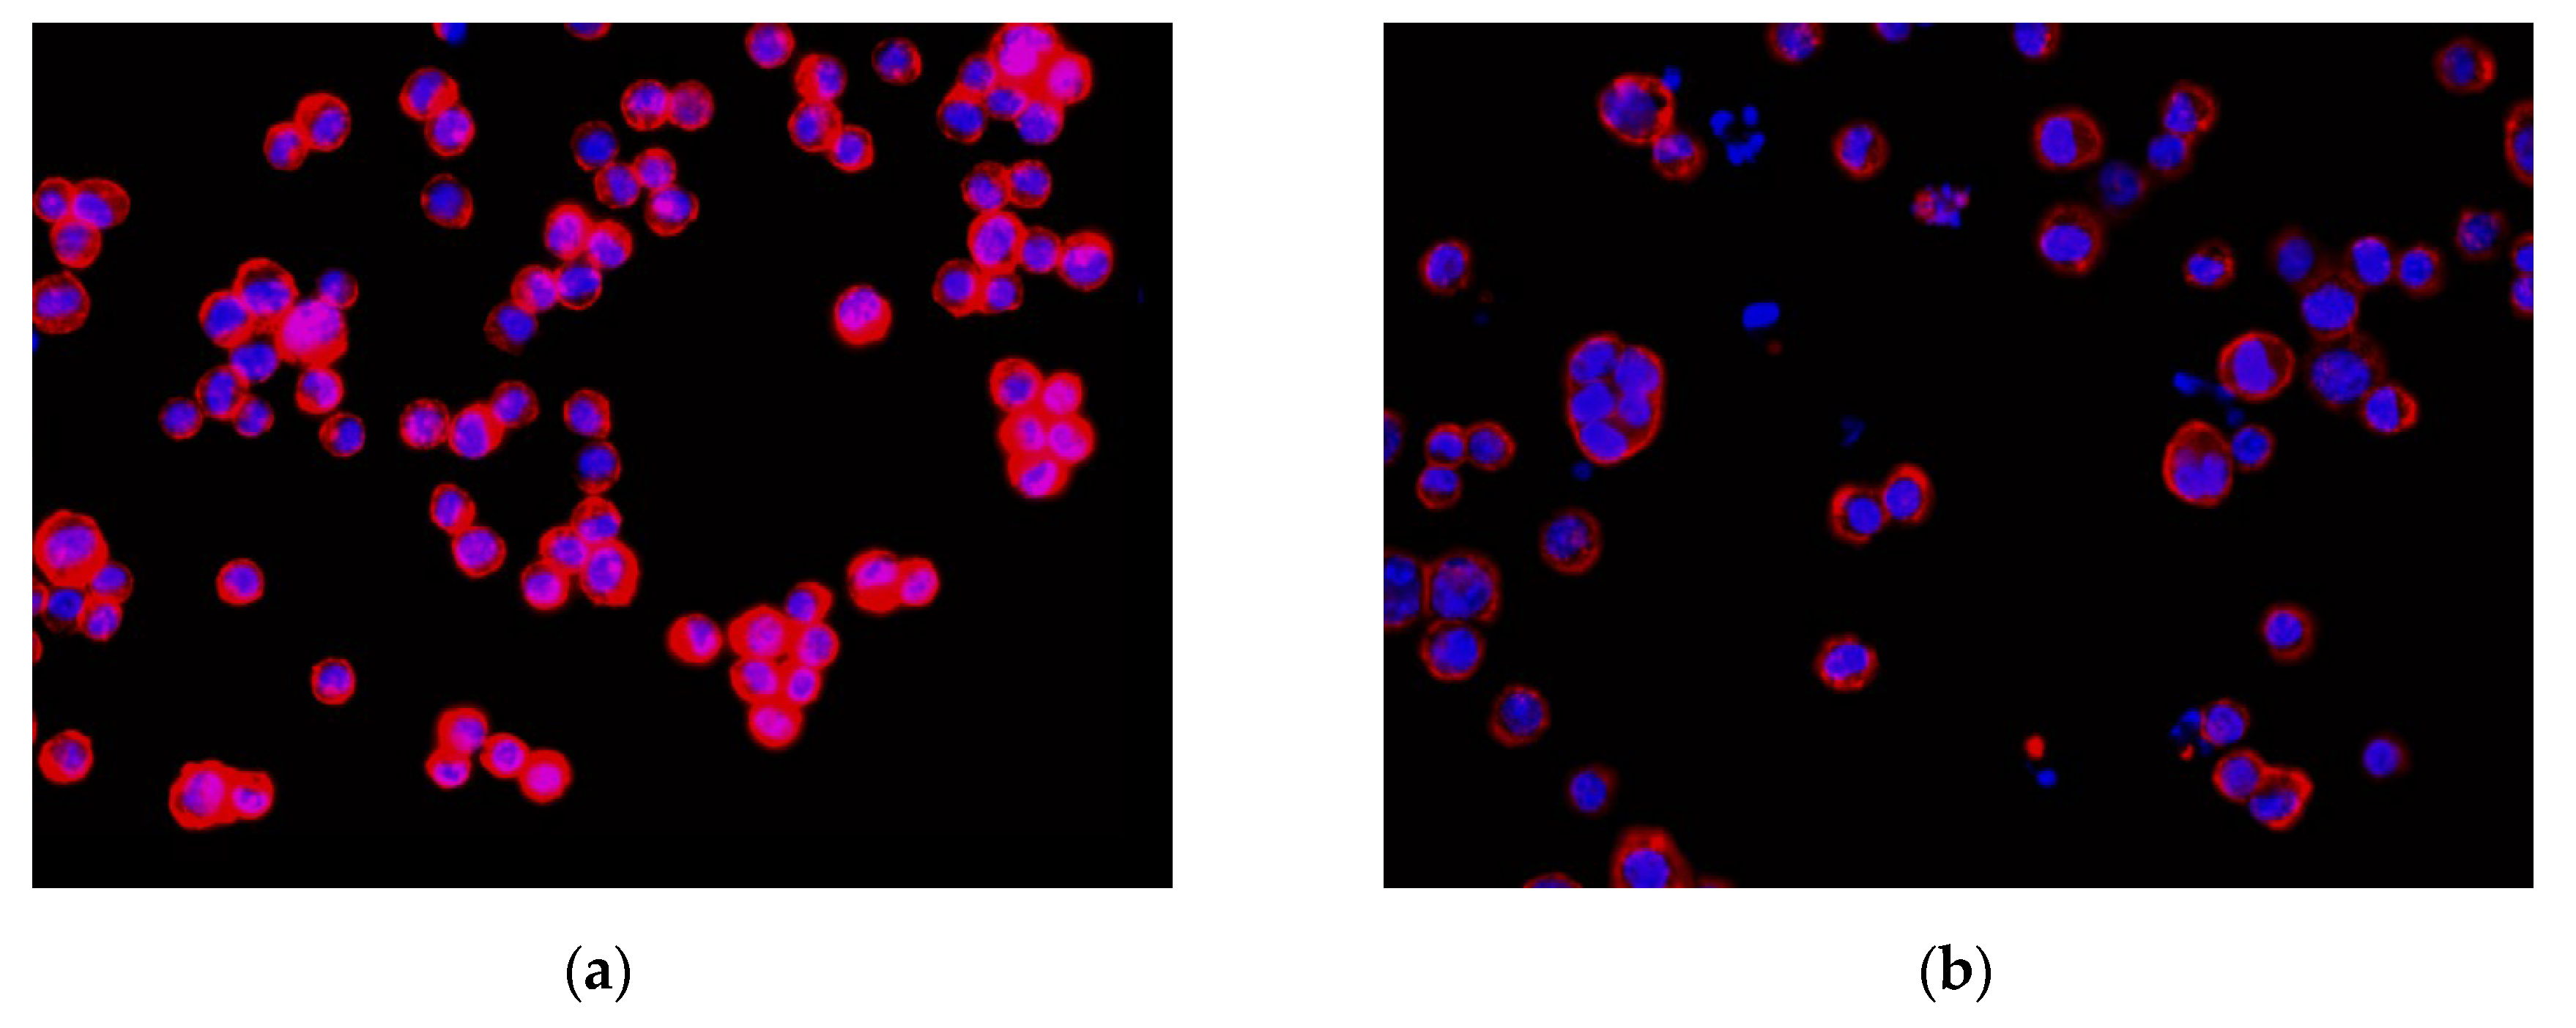

In this study, the experimental images were obtained from OLYMPUS D80 digital fluorescence microscopy photographs. The color image resolution was 1360 × 1024 (pixels), and the optical magnification was 40×. Figure 8 shows the equipment used. The image analysis algorithm was programmed using the C++ programming language. Moreover, the YOLO algorithm used in the study was programmed using the C++ programming language. The hardware of the computer included an Intel(R) Core(TM) i7 2.8 GHz Central Processing Unit and an Nvidia RTX 2060 Super Graphics Processing Unit graphics card for cell nuclei image training and executing the proposed method. The cell images included four human colon cancer cell lines (HCT116, DLD-1, HT29, SW480) [39], which were used for studying the treatment regimens and for drug screening. In the experiment, DAPI fluorescent dye was used to stain the cell nuclei and DNA in the cancer cells. Subsequently, rhodamine phalloidin was used to stain the cytoskeleton. Figure 9 shows the HCT116 cancer cell image that was obtained using a fluorescent microscope D80 camera (Figure 9a, untreated cancer cells (image no.4484) with dimethyl sulfoxide (DMSO); Figure 9b, cancer cells treated with dinaciclib (image no.4496)). Notably, dinaciclib (SCH-727965) is an inhibitor of cyclin-dependent kinases, and DMSO is a polar aprotic solvent. In Figure 9, the red color is the cytoskeleton, and the blue color is the cell nucleus. We used the cytoskeleton and cell nucleus images for analysis. As only the cell nuclei that are encapsulated by the cytoskeleton are considered to be intact cells and included in the cell enumeration, the cytoskeleton signal was only used to determine if the cell nucleus could be included for enumeration. The cell nuclei were then the primary analysis targets. The weighting data obtained from training were next used for cell nucleus recognition, while the image processing algorithm and CLSA were used to detect the cell nuclei with mitotic defects and the micronuclei. Experiments were then conducted to validate the performance of this method. The algorithm-related parameters and experimental results are described below.

Figure 9.

Colon cancer cell images of HCT116: (a) HCT116 cell with DMSO(dimethyl sulfoxide) (no.4484); (b) HCT116 cell with dinaciclib (no.4496).